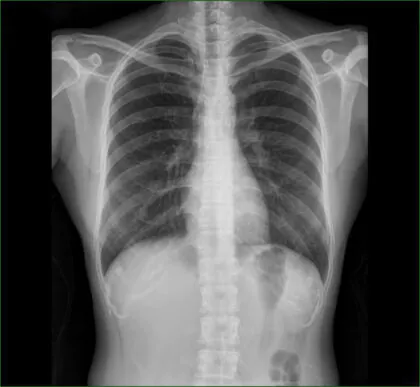

胸部レントゲン検査

心臓の大きさ、肺うっ血の有無、大動脈の状態などを評価します。